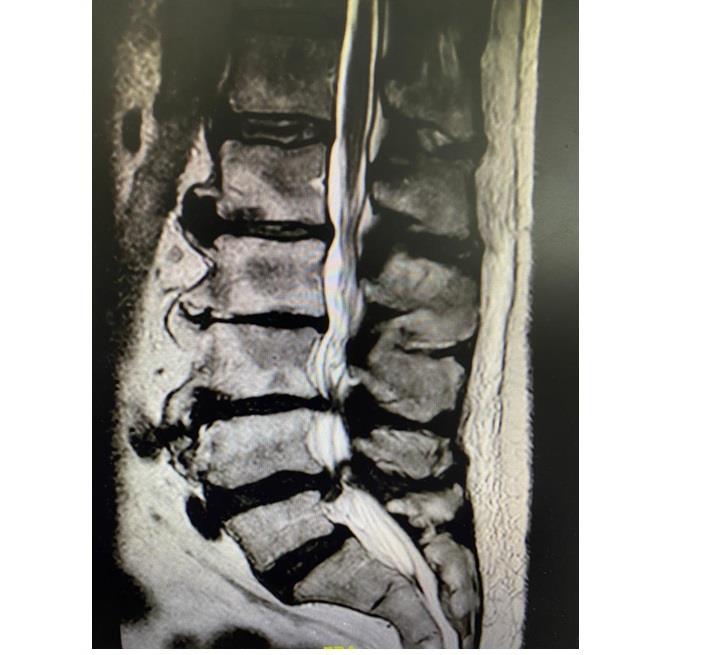

באדיבות ד"ר אלכסנדר ברוסקין

בשלב הראשון יבצע הרופא המטפל אנמנזה מקיפה ובהתאם לממצאים יפנה לבדיקת הדמיה מתאימה. אם קיים חשד להיצרות בעמוד השדרה המותני תתבצע בדיקת CT, בעוד שאם יש חשד לפגיעה בחוט השדרה תתבצע גם בדיקת MRI.